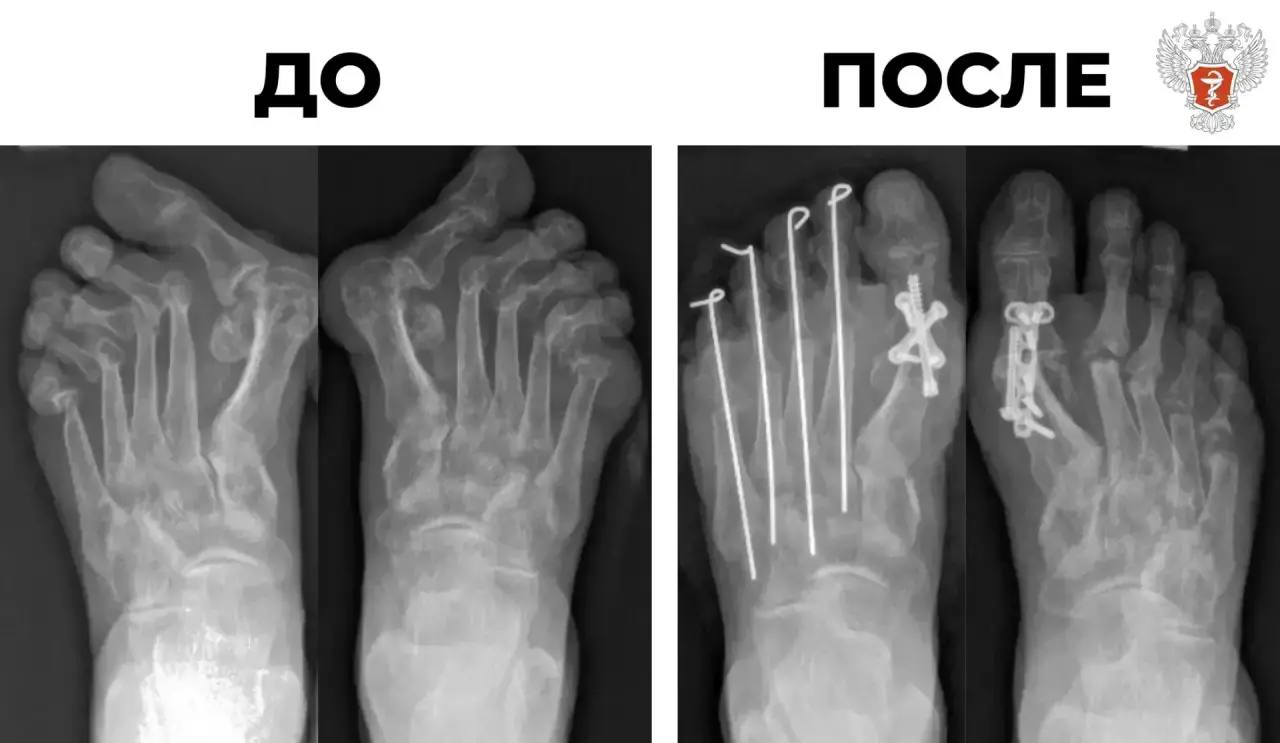

Специалисты федерального центра Минздрава России провели реконструкцию деформированных стоп

Пациентка поступила в Новосибирский НИИ травматологии и ортопедии им. Я. Л. Цивьяна Минздрава России с сильной деформацией десяти пальцев на ногах, вызванной ревматоидным артритом.

После лекарственной терапии врачи приняли решение о проведении операции Клейтона-Хоффмана для коррекции деформации, в ходе которой исправили вывихи малых пальцев и зафиксировали их спицами.

— Мы убрали разрушенные давящие головки плюсневых костей, тем самым добились снижения напряжения на тканях. Пальцы встают в правильное анатомичное положение, уходит подошвенное давление, — рассказал хирург-ортопед Новосибирского НИИ травматологии и ортопедии им. Я.Л. Цивьяна Минздрава России Матвей Лучшев.

Операция прошла успешно. Сейчас стопы пациентки работают правильно. В скором времени она сможет носить обычную обувь и продолжать лечение.